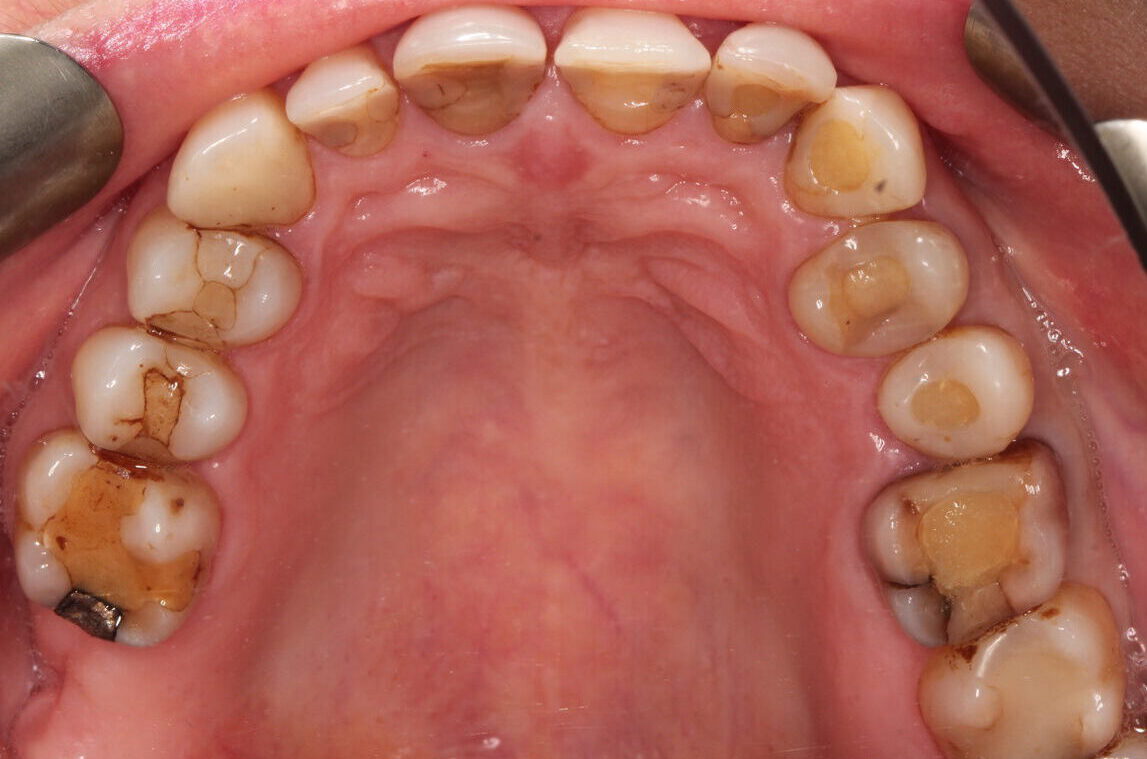

4. Nakłady (plomby) kompozytowe w zębach bocznych

wykonane w laboratorium